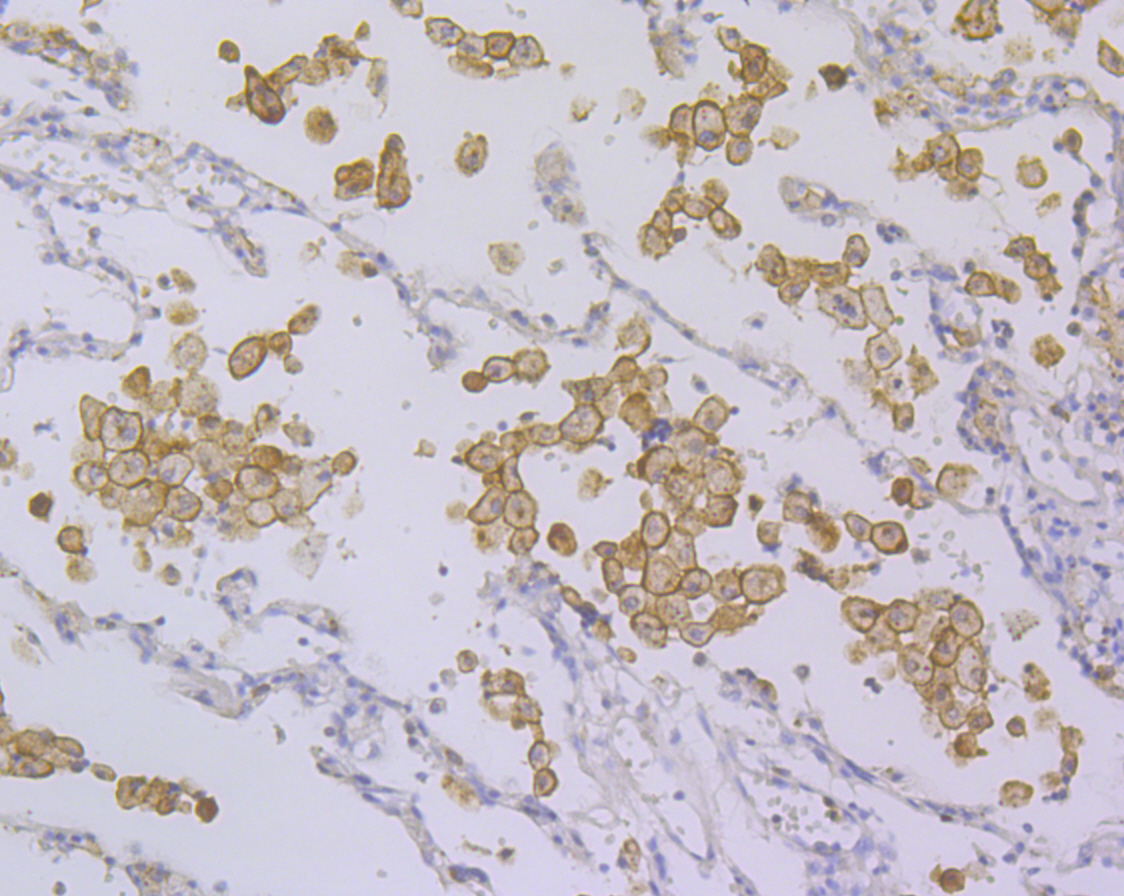

Immunohistochemical analysis of paraffin-embedded human lung cancer tissue using anti-DAP12 antibody. Counter stained with hematoxylin.